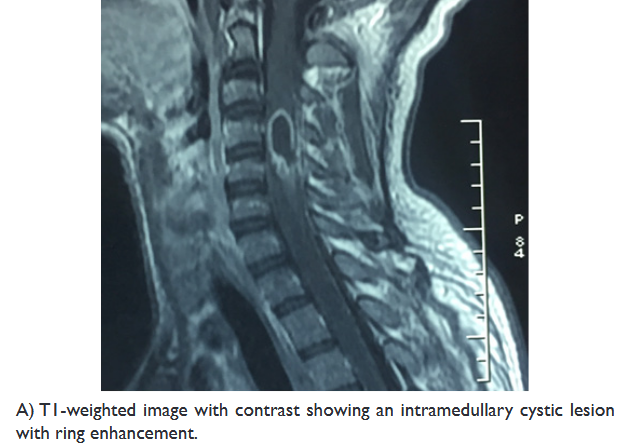

On examination, the muscle strength of the upper extremity was 2/5, and 3/5 in his lower extremity, with a positive Hoffman’s and Babinski’s signs. A spinal MRI revealed an intramedullary cystic mass, at level of C4, with ring enhancement after injection of gadolinium, associated with perilesional edema extending from the level of C2 to C7 (Figure 1).

Figure 1 Preoperative sagittal MRI of the cervical spinal cord.

Murphy et al. reported that the presentations of ISCA on MRI are similar to those of a cerebral abscess. In the early stages of infectious myelitis, MRI shows high-signal intensities on T2WI. The lesion reveals poorly defined enhancement on T1WI with contrast. One week later, the lesion becomes less diffusely hyper-intense on T2WI. The marginal enhancement is clearly defined on T1WI with contrast. Diffuse marginal cord edema was also noted.18

Also, a ring-enhancing spinal lesion is a nonspecific feature. Recently, Diffusion-Weighted MR has been added to the imaging techniques, as a more sensitive and specific method for the differential diagnosis of ISCA from spinal cord tumors such necrotic gliomas, metastatic and demyelinating lesions. The abscess has high signal intensity on DWI and low values of ADC.19